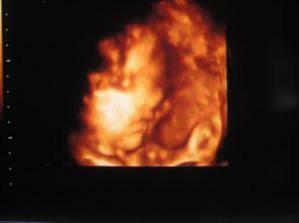

Karolínka :o)

naše neplánované mimíško,tuším holčičku a tu mi Dr.20 tt potvrdil :o)...termín porodu 19.12.2007